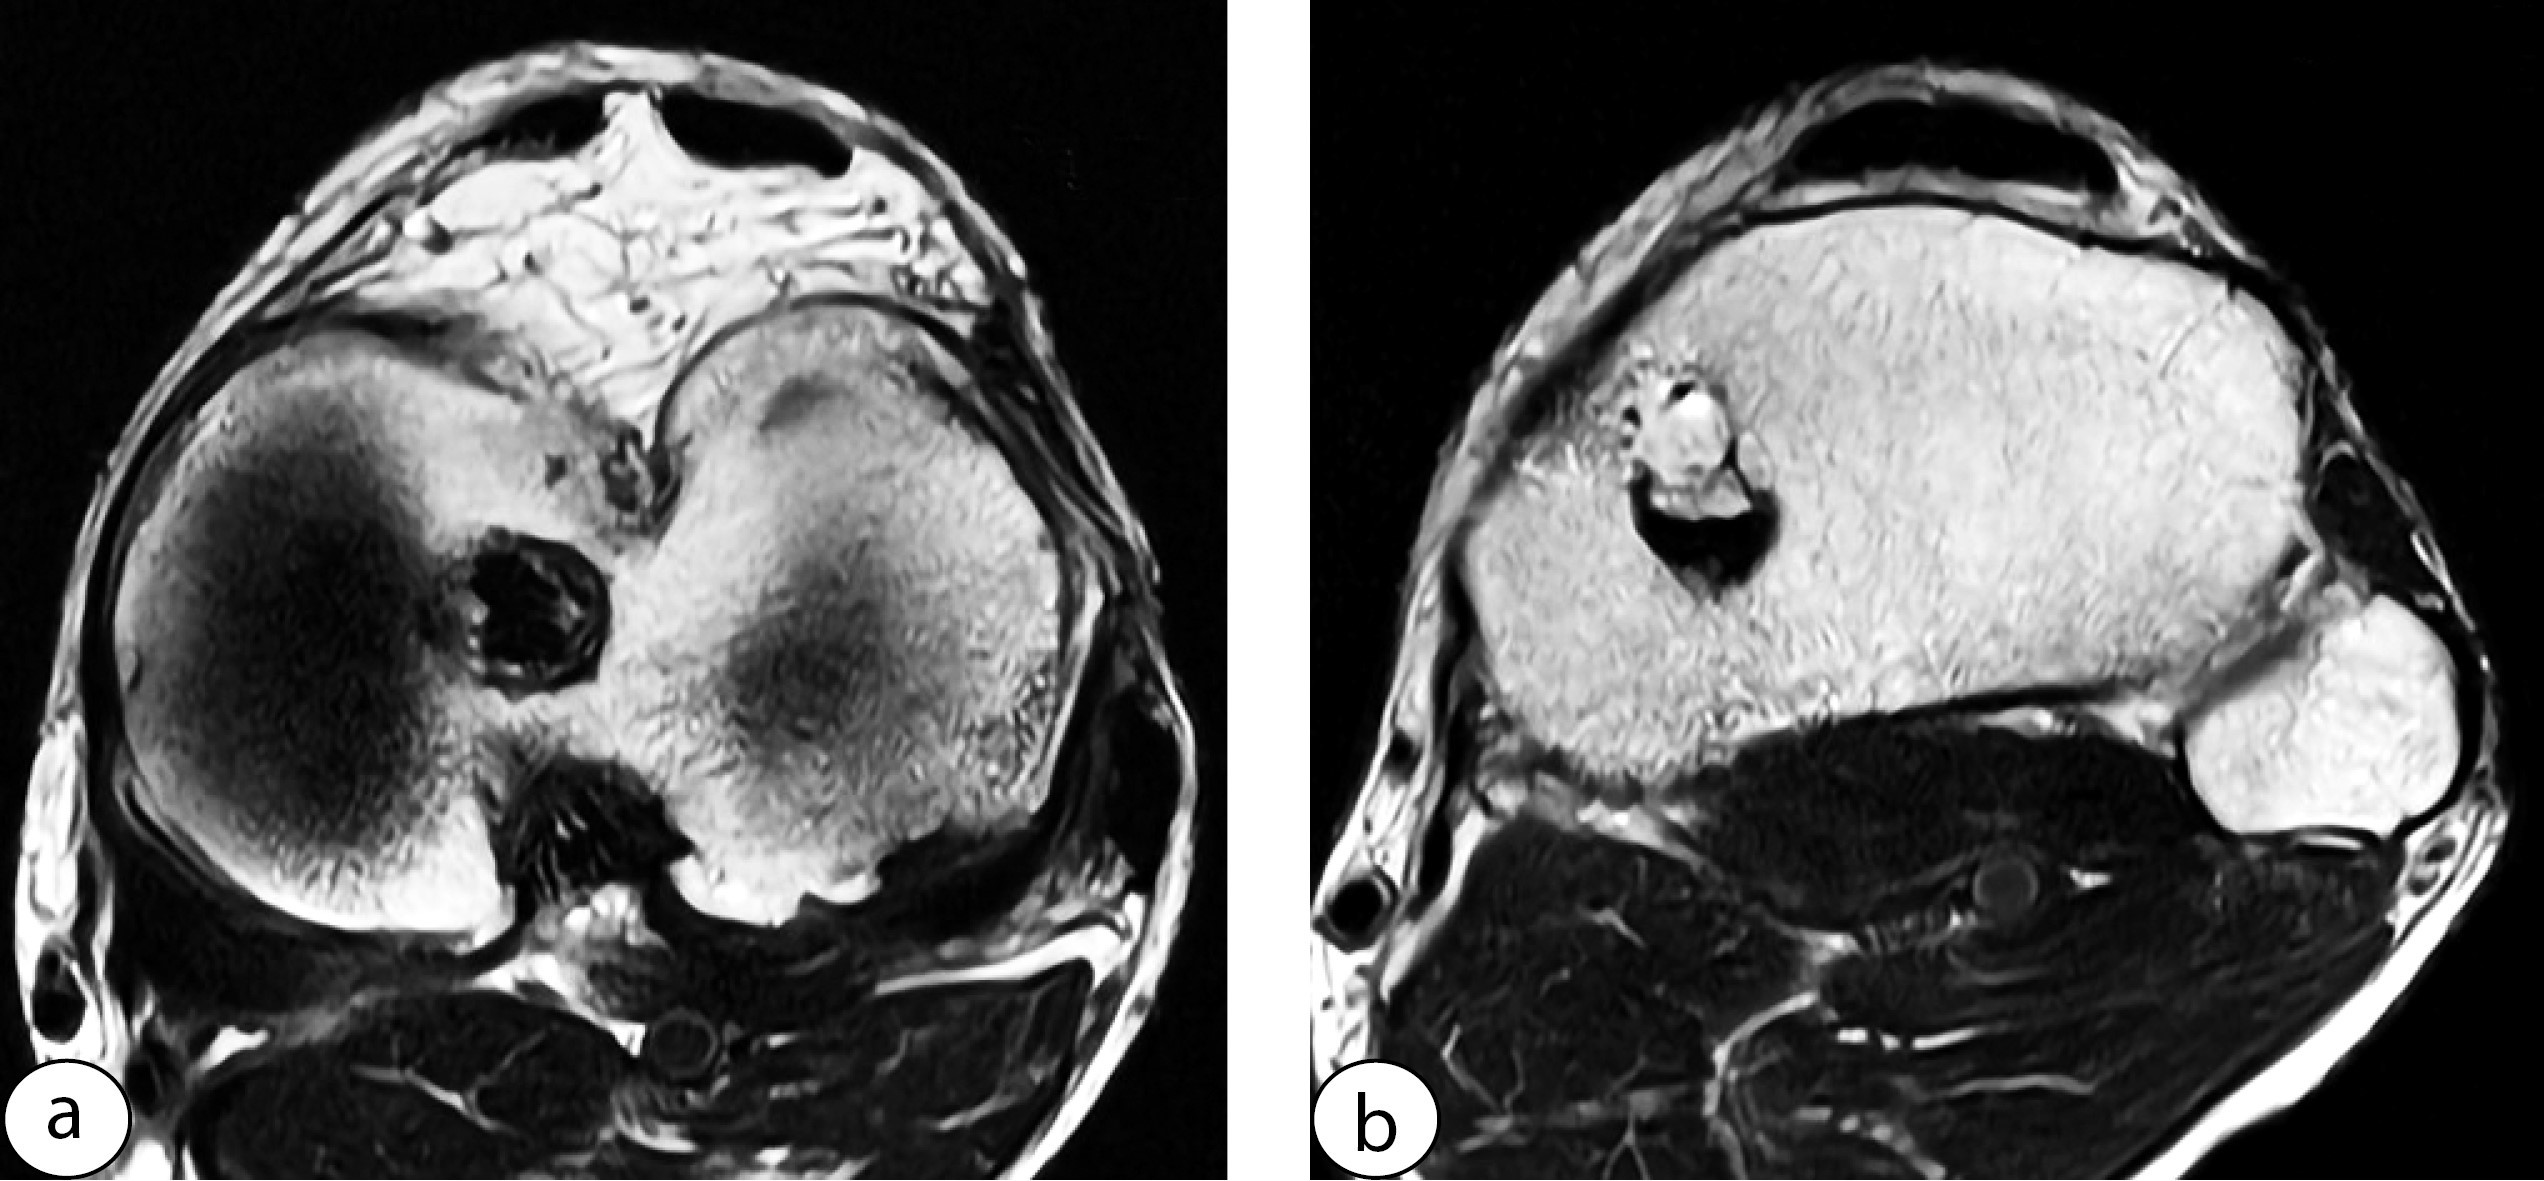

In all patients of the Group 2 who underwent graft harvesting with subsequent full-layer suturing of the defect, the ligament after surgery formed a unified structure. The suture line was either not visible or barely discernible. No tendon defects or deformities due to suture divergence were observed. The width of the ligament was almost completely restored, with only moderate thickening visible on all axial slices (Figure 5).

Figure 5. MRI scan of the patellar tendon in a patient from Group 2 before (a, b) and after graft harvesting (c, d)

Two patients with sutures placed at intervals of more than 2 cm and not across all layers exhibited areas of deformed and incompletely healed ligament (Figure 6).

Figure 6. Appearance of the deformed patellar tendon after graft harvesting with non-full-thickness suturing: tendon edges are approximated but not sutured (a), only the superficial layer and peritenon are sutured (b)